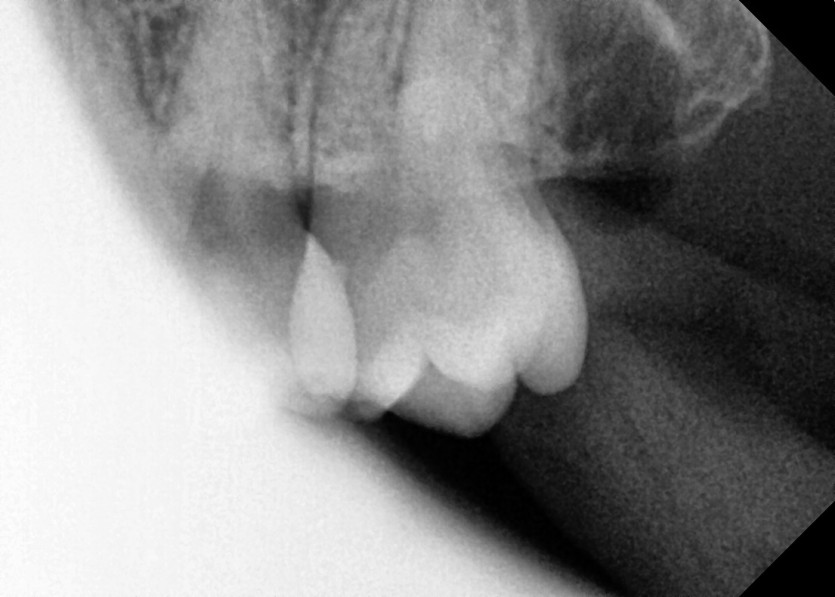

#28,38 사랑니 발치

구강 외과 전문의가 당일 발치했습니다.